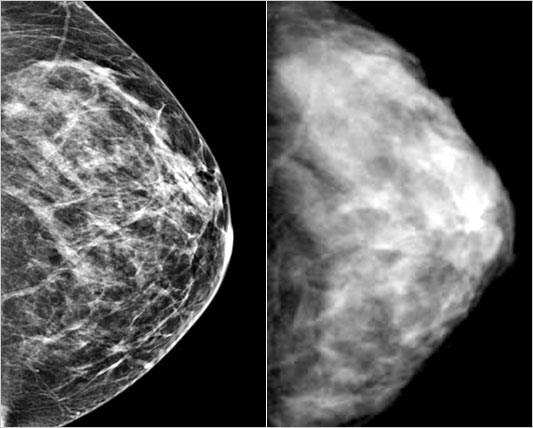

L’eta’ per il primo esame va portata per tutte le italiane ai 45, come indicano le evidenze scientifiche. A lanciare questo appello alle Istituzioni sono i piu’ autorevoli oncologi mondiali, riuniti fino a domani a Modena per il Convegno internazionale “Meet the Professor”, un appuntamento scientifico di primo livello interamente dedicato al cancro della mammella.

E proprio il modello emiliano viene portato come esempio: questa regione, prima in Italia, dal primo gennaio anticipera’ lo screening di 5 anni rispetto allo standard ad oggi. Dai 45 ai 50 la mammografia va ripetuta ogni 12 mesi, dopo ogni 24. “Una misura da estendere al piu’ presto in tutto il territorio nazionale – afferma il professor Pierfranco Conte, direttore del Dipartimento Integrato di Oncologia ed Ematologia del Policlinico universitario di Modena, presidente del Convegno -. Grazie all’effetto combinato di diagnosi precoce e maggiore efficacia delle terapie, oggi la sopravvivenza per questo tumore, che colpisce 38.000 italiane ogni anno, supera il 90%. Ma resta la piu’ frequente causa di decessi nel sesso femminile fra i 35 e i 44 anni, con 7.800 casi stimati nel nostro Paese nel 2008. Vanno quindi sensibilizzate le donne ad aderire alla mammografia ma e’ soprattutto necessario che le Istituzioni siano pronte a recepire le indicazioni che provengono dalla comunita’ medico-scientifica. Siamo ormai tutti concordi: la soglia deve essere 45 anni. E ancor prima quando vi siano particolari fattori di rischio come altri casi di neoplasia in famiglia”. Modena si conferma una punta di eccellenza dell’oncologia, anche grazie a collaborazioni con prestigiosi centri. Fra questi L’M.D. Anderson di Houston (Texas) il piu’ grande ed importante al mondo, guidato dal prof. Gabriel Hortobagyi che co-presiede il Convegno.